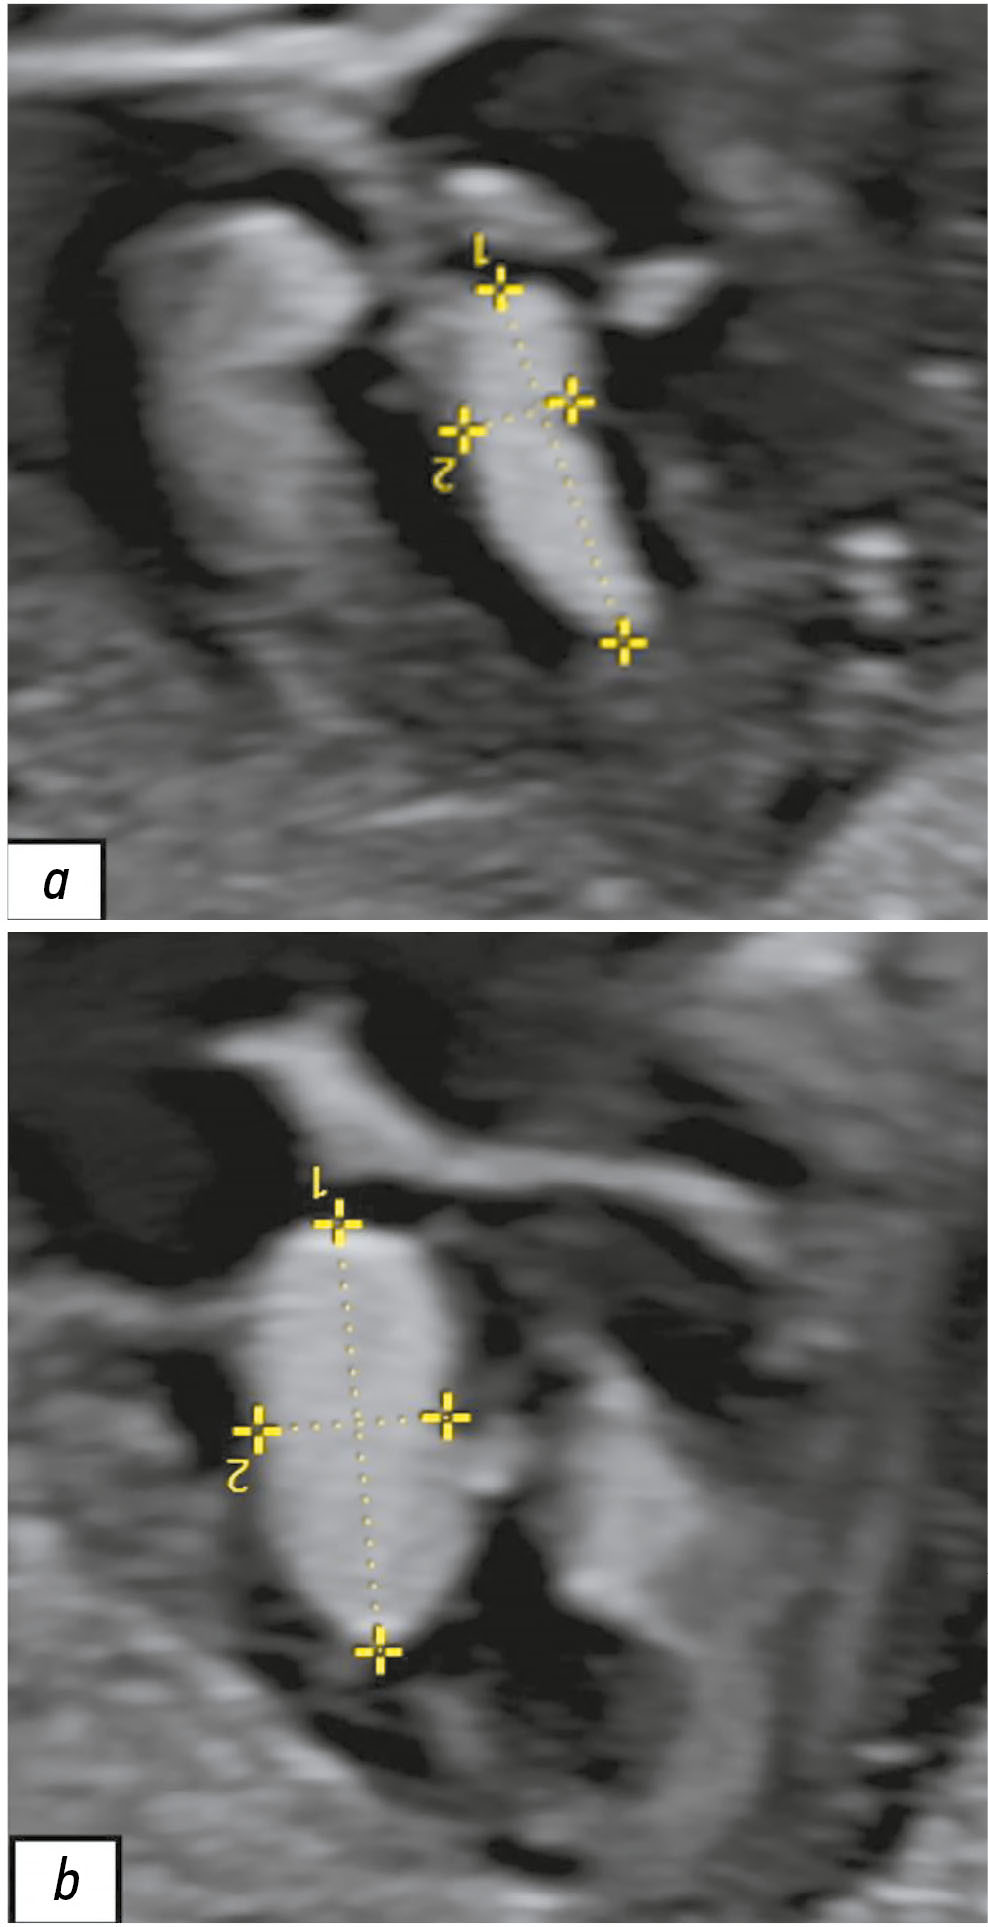

Early detection of orphan diseases, including tuberous sclerosis complex, requires a multidisciplinary approach and the integration of new prenatal diagnostic methods, utilizing ultrasound and magnetic resonance imaging. Accumulated knowledge of the clinical manifestations of tuberous sclerosis complex and advancements in diagnostic techniques enable the identification of this condition. Magnetic resonance imaging allows for high-quality anatomical and functional imaging of the brain in various planes, improving the sensitivity and diagnostic value of the method for early (prenatal) detection of cerebral manifestations of tuberous sclerosis complex. Additionally, magnetic resonance imaging detects mediastinal masses. This highlights the need for a comprehensive approach in diagnosing tuberous sclerosis complex, with magnetic resonance imaging as the primary method for assessing the fetus’s cardiovascular and central nervous systems.

This article presents a clinical case of tuberous sclerosis complex determined by intrauterine diagnosis followed by postnatal examination of the newborn and genetic confirmation of the diagnosis. This case report demonstrates the diagnostic value of magnetic resonance imaging in the prenatal diagnosis of tuberous sclerosis complex.